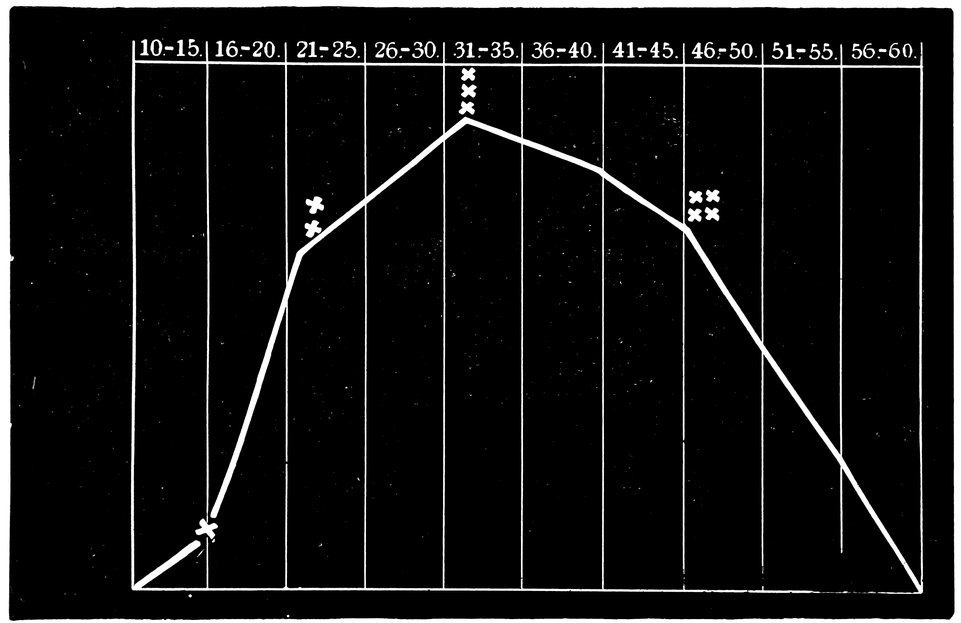

To illustrate this fact, I have drawn up a curve of the sexual life of woman, making use of the statistical data available in central Europe regarding the age at which menstruation first appears, the age at which maidens marry, the age at which the largest number of women give birth to a child, and the age at which menstruation ceases; and reducing the figures to averages. * denotes the fifteenth year of life, as the average age at the menarche; ** denotes the twenty-second year of life as the average age at marriage; *** denotes the thirty-second year of life, in which woman exhibits her maximum fecundity; **** denotes the forty-sixth year of life as the average age at the menopause. (Fig. 1.)

Fig. 1.—Curve of the sexual life of woman from the tenth to the sixtieth year of life.